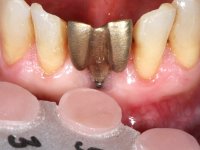

With the implant osteo-integrated with did an impression (open-tray technique) and the dental technician started the construction of a gold framework. The use of an abutment made of a gold alloy allowed us to do a framework with a perfect fit.

During the framework try-in, the color survey was done in order to proceed with the ceramics placement, with a crown and gingiva-components.